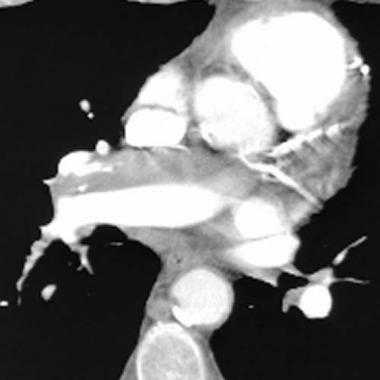

Спиральная КТ с контрастным усилением позволяет законтрастировать просвет легочных сосудов и увидеть тромб в их просвете. У молодого мужчины после межконтинентального перелета возникла острая боль в груди и нарушение дыхания. КТ визуализирует тромб в артерии переднего сегмента верхней доли левого легкого ( LA 2) и артерии переднего сегмента верхней доли правого легкого ( RA 2).